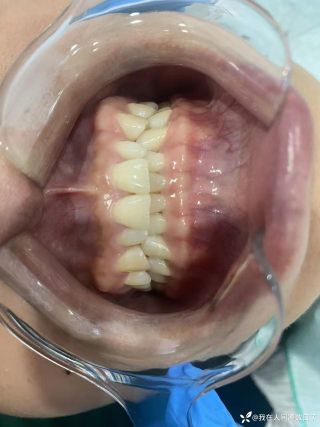

烧伤整形邹普功烧伤科医师

活动背景和目的:我从去年九月份陆续在丁香园写了几十帖有关腋臭微创手术的帖子,受到很多同行老师的关注及跟帖,其中有很多同行老师也在尝试用我的这种方法治疗狐臭,并且收到很好的效果。随着站内外科同行对狐臭微创手术的关注度日渐增高,近期受丁香园邀请,特举办一次关于狐臭微创手术的跟学练活动。这也是本人根据临床工作中的一些手术案例总结的经验,分享给大家一起交流学习。让我们一起做好除臭这件事!各位站友可点击下面狐臭专场链接交流学习(包含本人视频操作教学详解、常见问题讨论和各位站友同行的手术佳作):https://3g.dxy.cn/newh5/view/nodeActivityTopic/270第一期我给大